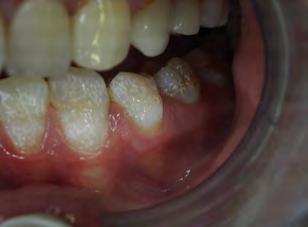

Two authors had access to the data and all information was de-identified. Study personnel made no contact with patients at any time throughout the study, and no PHI was recorded. Re corded data included diagnosis (clinical and/or pathologic), basic demographics (age, gender), and current prescription medica tions. For cases that were not biopsy-proven, the standard clinic protocol is that the clinical presentation must exhibit the charac teristic white Wickham striae for a patient to be given the clinical diagnosis of OLL or OLP (Figure 1). Any clinical diagnosis of OLL or OLP was rendered by one of four oral medicine experts in the Oral Medicine Clinic, and biopsy was performed in cases with any doubt.

Figure 1. Example of characteristic Wickham striae and reticular pattern on buccal mucosa used to clinically diagnose OLL and OLP cases. Erythematous areas also seen. Figure 2. Frequency and percent of study patients using specific medications with color-coded drug classes.